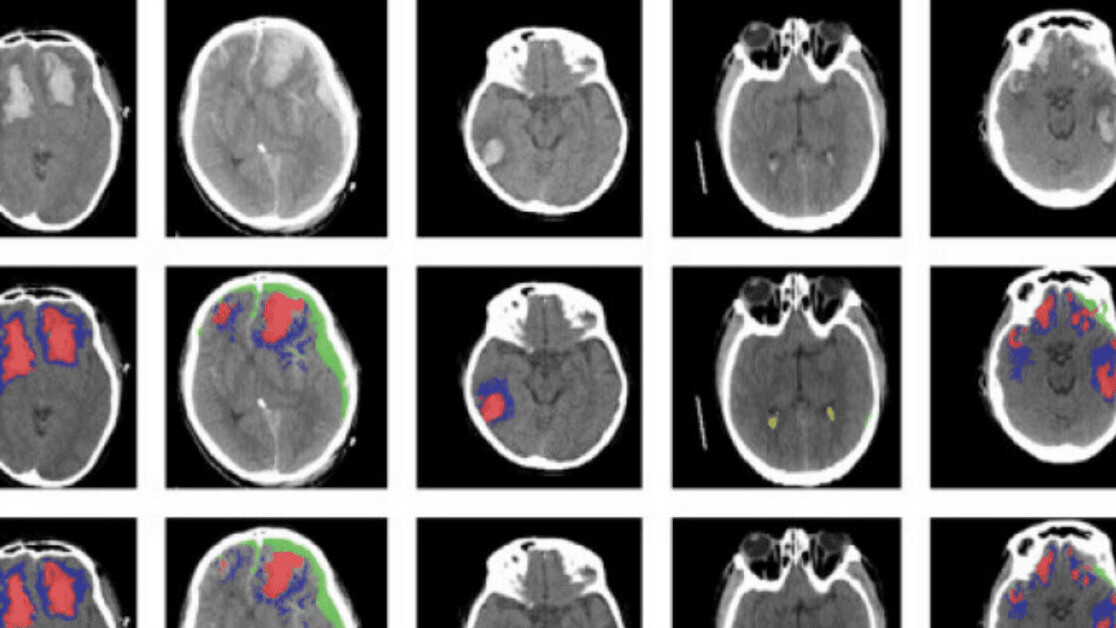

A new AI tool can automatically identify different types of brain injuries by analyzing images of CT scans.

The system uses a machine learning algorithm to detect and differentiate between types of brain lesions — areas of tissue that have been damaged through injury or disease.

The system is based on an artificial neural network developed at Imperial. The researchers trained the tool on more than 600 CT scans showing different types of brain lesions. They then checked if it worked by applying it to an existing dataset of scans.

They found that the AI successfully classified individual parts of each image — and worked out whether the brains were damaged or not.